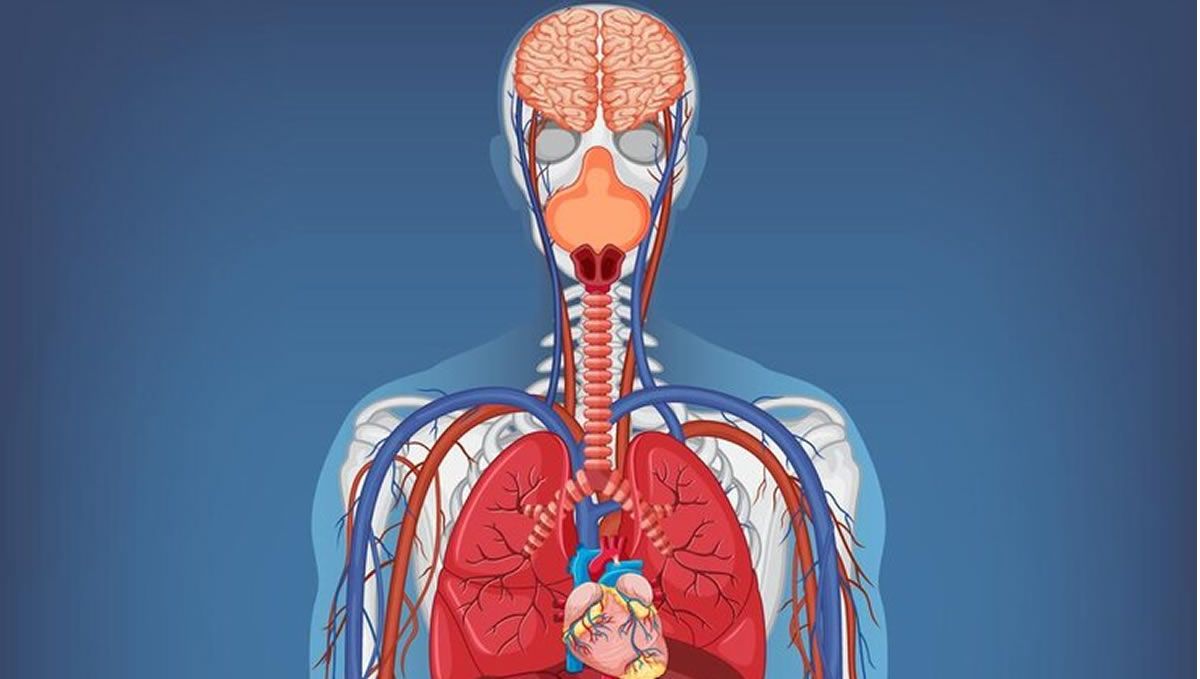

El cuerpo humano está formado por múltiples órganos que ayudan, en conjunto, a su correcto funcionamiento. Y aunque algunos, los considerados vitales, son indispensables para la vida, hay otros que no son tan conocidos y cuya pérdida no nos impide seguir viviendo.

El primero de ellos es el bazo, un órgano que ayuda a filtrar la sangre y a combatir infecciones. Sin embargo, apunta @lahiperactina, hay personas a las que les ha sido extirpado por diversos motivos, como un accidente. El segundo es el apéndice, “un órgano pequeñito en forma de tubo unido a la primera parte del intestino grueso”.

Le siguen las amígdalas, “dos bolas de tejido que tenemos a los lados de la garganta”. “Son una defensa del sistema inmunológico contra las bacterias y los virus que inhalamos o ingerimos, y cuando se inflaman o se infectan repetidamente -lo que se conoce como amigdalitis- te pueden recomendar su extirpación”, explica.

Sandra Ortonobes deja los dos últimos puestos del ranking para dos de los órganos más conocidos del cuerpo humano: Los pulmones -“pero solo uno de ellos, no te pases”- y los riñones. “Podemos vivir con un solo pulmón, pero puede ser que tengamos menos capacidad pulmonar y resistencia física”, indica sobre los primeros. “Hay muchas personas que donan un riñón y llevan una vida completamente normal”, concluye con los segundos.